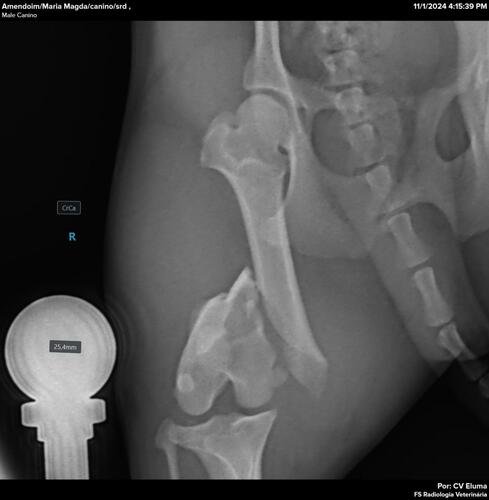

Ajude na cirurgia do fêmur do Amendoim

O Amendoim foi atropelado e abandonado nas ruas com um fêmur quebrado, mas foi resgatado e está internado, aguardando a cirurgia que ficou no valor de R$2.740,00 que precisa ser paga para que ele possa ser operado.Pedimos ajuda com qualquer ver tudo

O Amendoim foi atropelado e abandonado nas ruas com um fêmur quebrado, mas foi resgatado e está internado, aguardando a cirurgia que ficou no valor de R$2.740,00 que precisa ser paga para que ele possa ser operado.

Pedimos ajuda com qualquer valor!